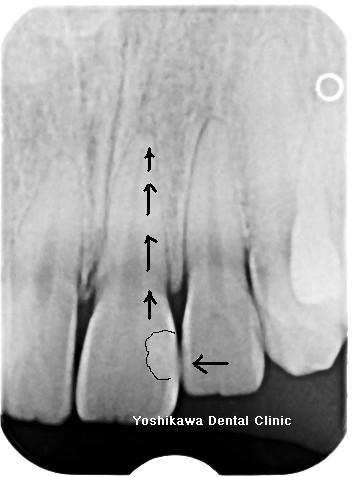

前歯が虫歯になった時は歯と同じ色の詰め物をすることが一般的ですが、稀に歯と詰め物の間に隙間があるとそこから漏れが起こり細菌が歯の中に侵入して、根の先に病巣・膿がたまることがあります。レントゲン写真です。